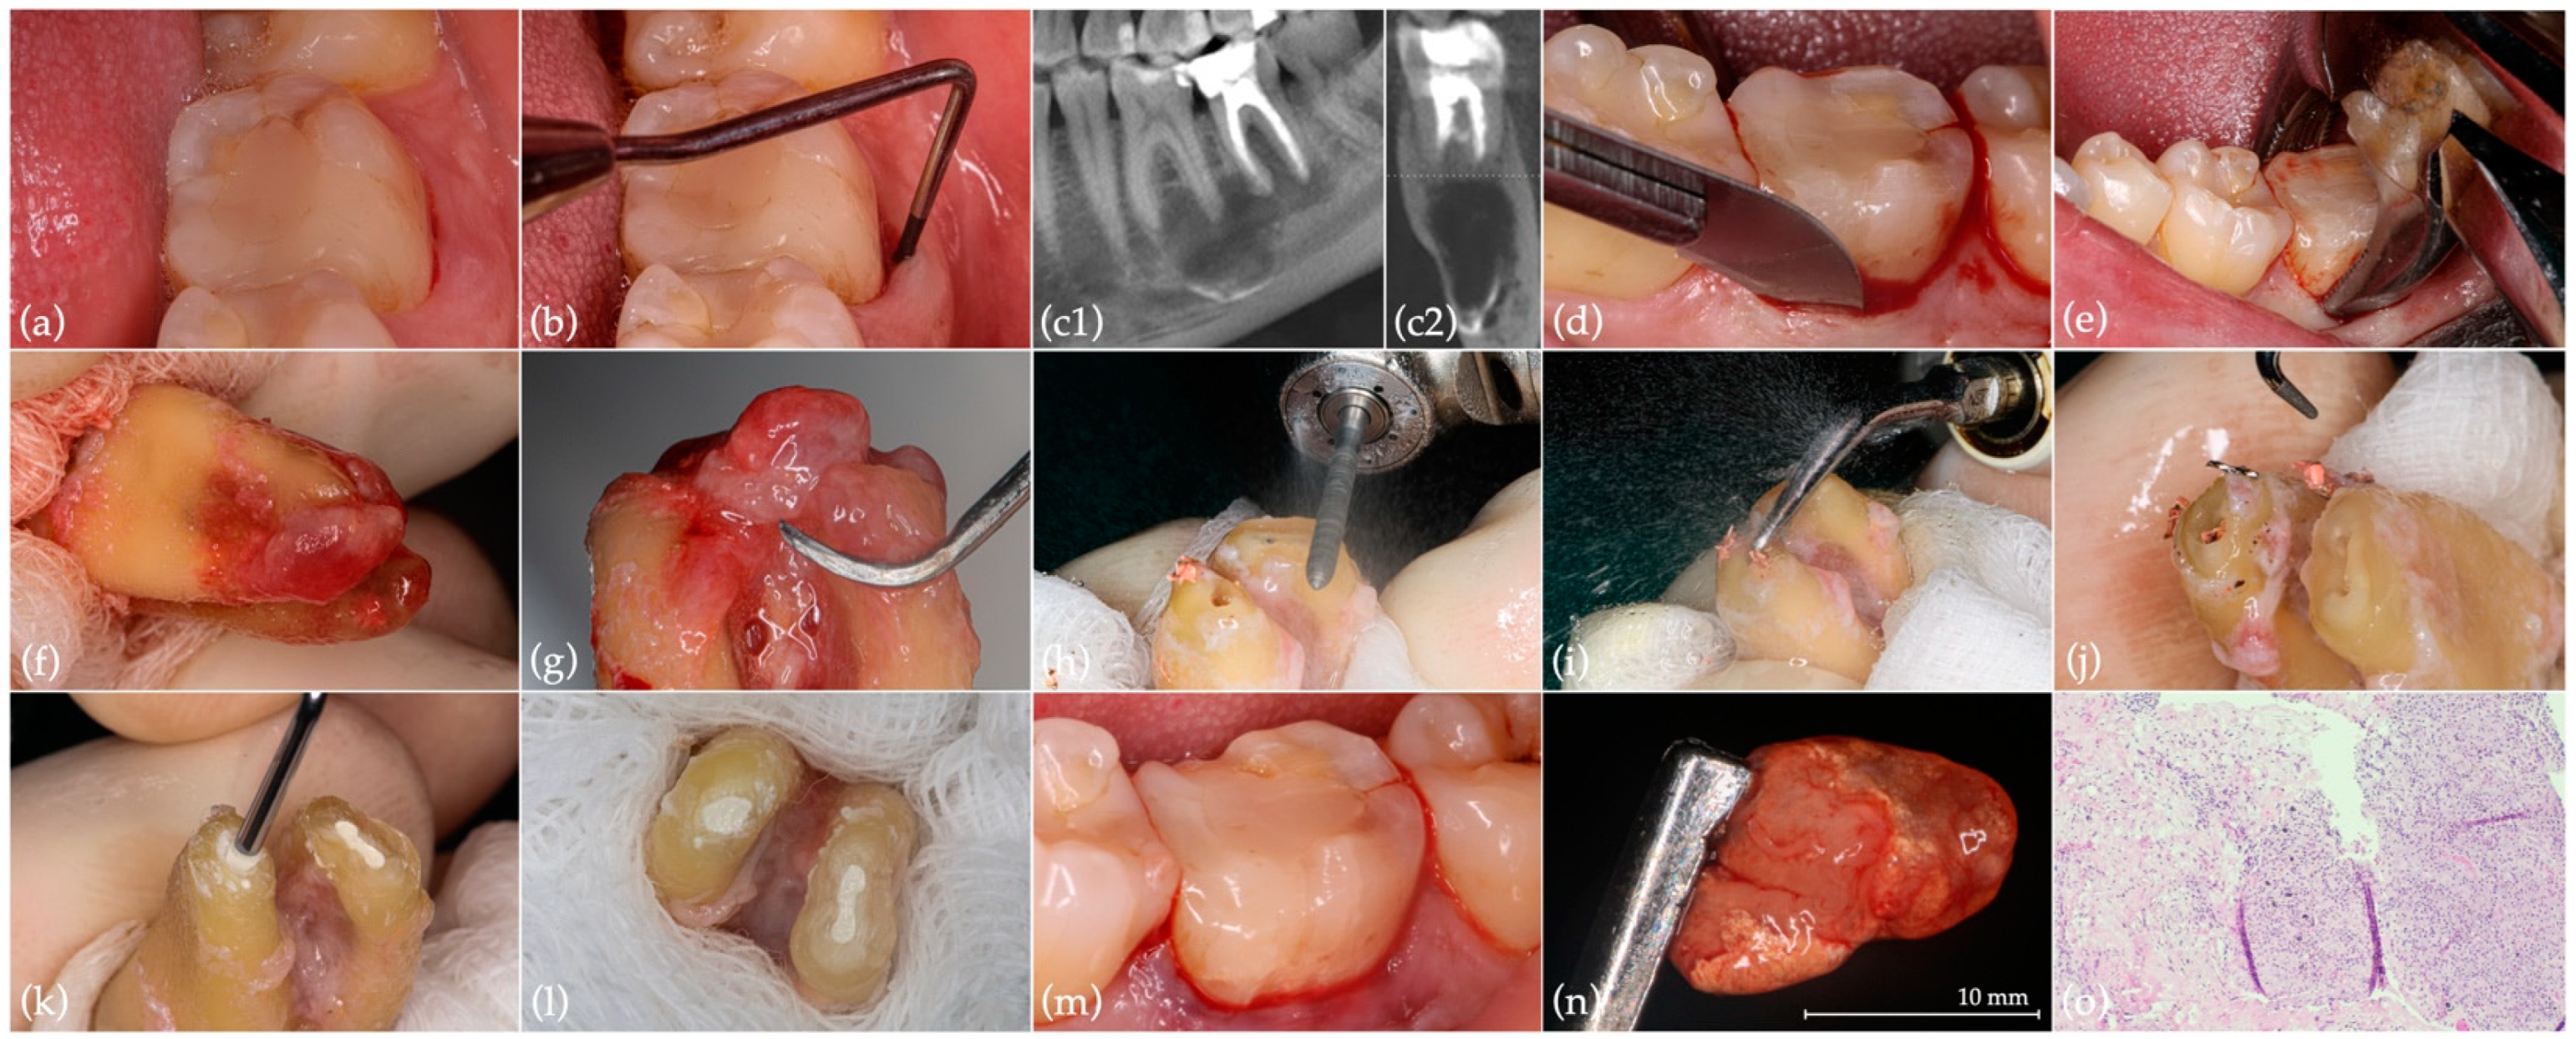

2.1. Intentional Replantation

2.2. Extraction with Alveolar Ridge Preservation Using Leukocyte-Platelet Rich Fibrin (L-PRF)

2.3. Implant Surgery